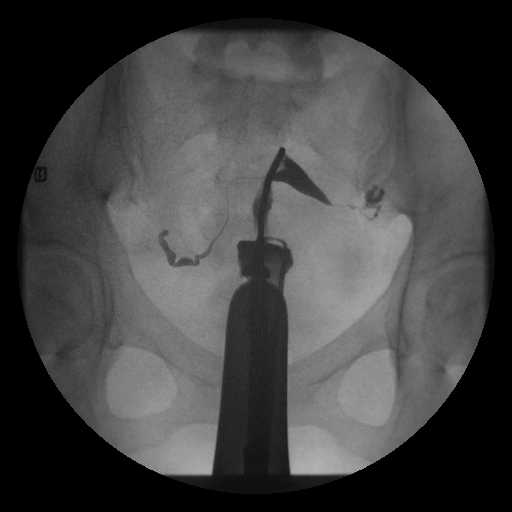

骨盆腔沾粘之攝影

顯影劑進入輸卵管

顯影劑進入輸卵管示意圖